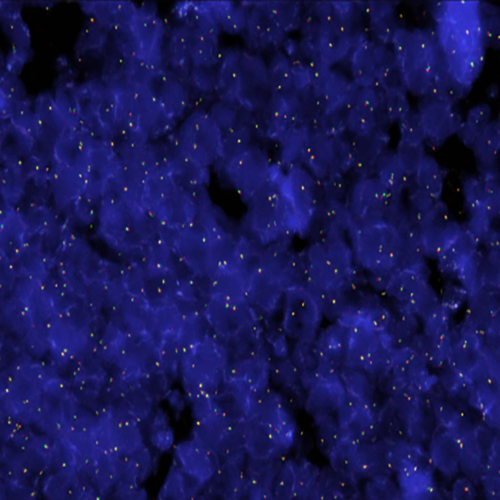

BCL2 / IGH t(14;18) probe hybridized to a normal interphase/metaphase (2R2G).

The t(14;18) chromosomal translocation is a common cytogenetic abnormality in human lymphoma and is observed in about 85% of follicular lymphoma (FL) and up to one-third of diffuse lymphomas (DL). Two breakpoint region clusters (BRC) have been identified: a major breakpoint region (mbr) within the 3' untranslated region of the BCL2 proto-oncogene (approximately 60% of the cases) and a minor cluster region (mcr) 30 kb 3' of BCL2 (approximately 25%). The BCL2 / IGH t(14;18)(q21;q32) specific FISH probe is optimized to detect the reciprocal translocation t(18;14), involving either of the two brc in the BCL2 gene in a dual-color, dual-fusion assay. Kreatech has optimized this FISH probe for the specific use on cell material (KBI-10606), or on tissue (KBI-10755).